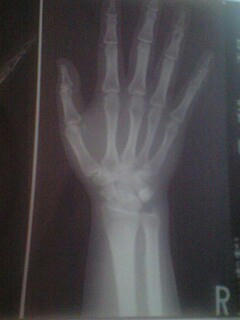

初診の時に持って行く為に預かった

自分の右手のレントゲン写真。。

骨はキレイ。

異常所見ナシ。

しいて云うならがっしりしすぎ?

骨格マニアなのでうはうは観賞(笑